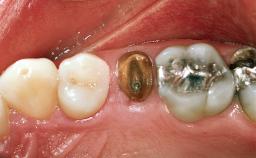

In November 2001, a 53-year-old female presented seeking advice and options for treatment of her maxillary incisor teeth. She was dissatisfied with both the functional and esthetic qualities of her existing restorations. Her medical health was excellent, and she reported no contraindications to dental care. On presentation, the patient’s dental health was less than ideal. Although she had no probing depths greater than 3 mm, she suffered from generalized chronic adult periodontitis and displayed multiple sites of bleeding on probing. Her remaining dentition was heavily restored, and many teeth had been endodontically treated. Areas of recurrent dental caries were noted on many teeth. Radiographically and clinically, the maxillary incisor teeth exhibited large areas of active caries, and after the splinted crowns had been removed, the teeth were determined to be non-restorable.

Prosthodontic Status of Neighboring Teeth Virgin Restored

Width of Edentulous Span 1 tooth (>= 7 mm) 1 tooth (< 7 mm) 2 teeth or more